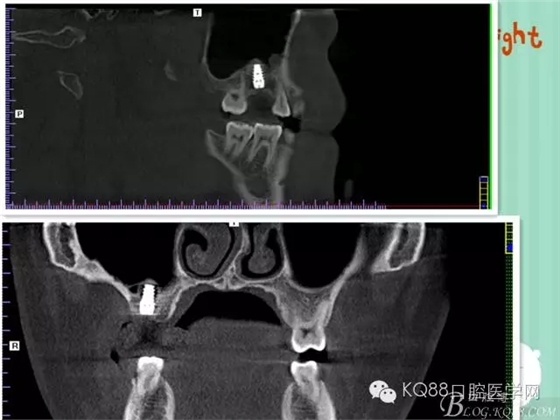

下面是拔牙前 CBCT

清晰可見(jiàn)根尖部陰影區(qū)域明顯。遠(yuǎn)中頰根

近中頰跟,同時(shí)可以看出離上頜竇比較近,且伴有骨缺損。

這個(gè)切面可以看到根裂。